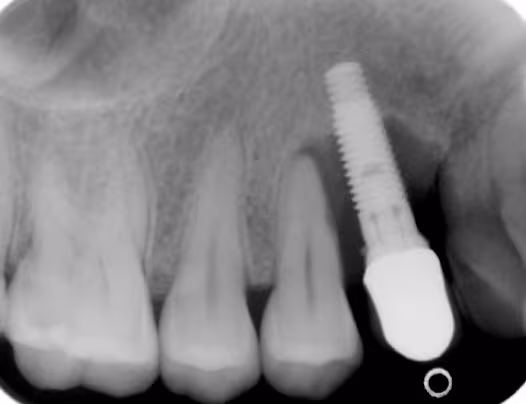

Peri-implantitis is the next step that occurs if peri-implant mucositis is not arrested and is allowed to progress resulting in loss of supportive bone. Peri-implantitis is considered to be a plaque-associated disease, thus plaque control and regular maintenance care are paramount. Risk indicators include a past history of severe periodontitis, poor plaque control, and failure to attend regular maintenance appointments after implant placement. Another factor that has been considered is poor positioning of the implant preventing good plaque removal. Increased probing depths, inflammation, possible recession and radiographic bone loss are used to diagnose this condition. Pocket depths have been noted to be correlated with bone loss and thus are used to determine the severity of the disease. If bone loss becomes extensive, mobility of the implant will occur.

Image Courtesy of Dr. C. Cobb.